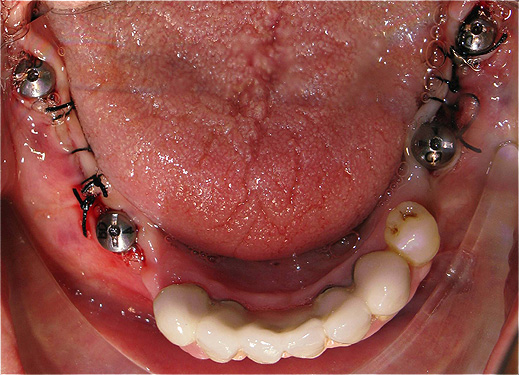

Caso 3 - Desdentado total reabilitado com prótese acrílica removível inferior, barra e clips para retenção e estabilidade

![]() |

![]() ![]() |